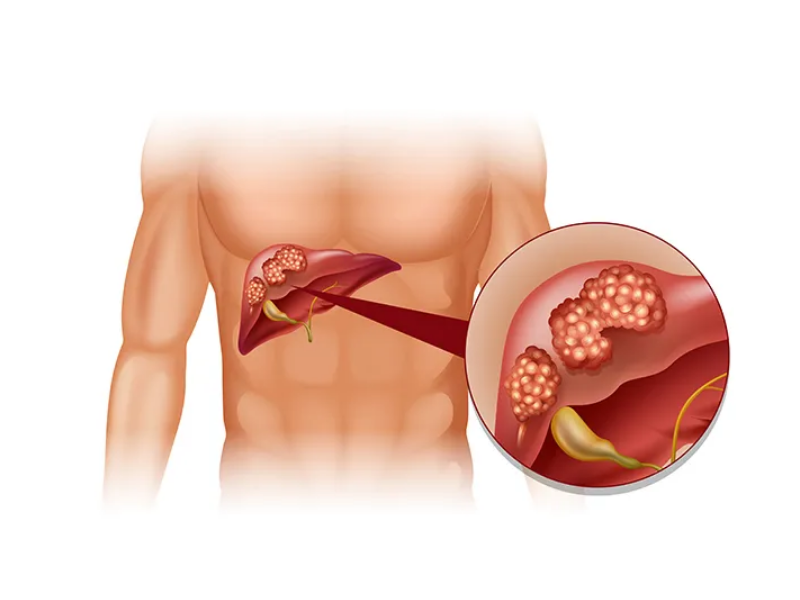

Liver transplant is a complex but life-saving procedure for patients with severe liver disease, liver failure, or certain liver cancers. It involves replacing a diseased liver with a healthy one from a living or deceased donor. At our Liver Transplant and HPB Surgery Care center, we provide comprehensive care for both adults and children, ensuring safety, precision, and excellent outcomes.